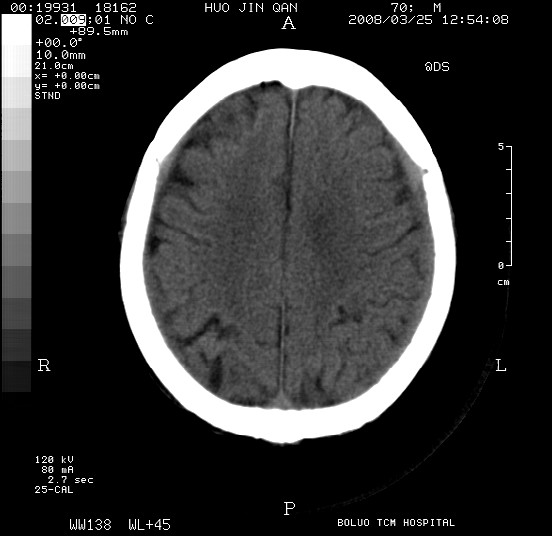

以下是引用随光逐影在2008-3-25 20:15:00的发言:[br]双侧额颞顶部亚急性(或慢性)硬膜下血肿。

以下是引用liuyue在2008-3-26 18:57:00的发言:[br]以下是引用随光逐影在2008-3-25 20:15:00的发言:[br]双侧额颞顶部亚急性(或慢性)硬膜下血肿。 [br]支持![br]可以无明显外伤病史,老年人可以在激烈摇晃或轻微头部碰创头部时,发生硬膜下出血.